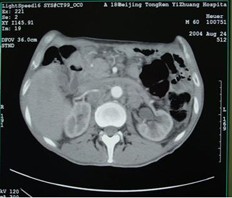

女,40岁,2006年10月底确诊为胃腺癌(皮革胃),腹腔淋巴结转移;2006年11月外科手术时见腹腔广泛转移(粘连),病灶无法切除(下图1a,b),预期生存期低于3个月;留置(胃)造瘘管。2006年12月开始今又生联合化疗治疗,今又生2×1012VP,室温下自行融化后加入到100ml生理盐水中,30~40分钟内静脉滴注完毕,1/次/周,连续使用6周。今又生给药三天后静脉化疗。2007年7月外科手术拔除造瘘管;2007年9月随访,患者状况良好,无复发。

2a 治疗前 主动脉前方,胃底和脾门之间见大量结节状淋巴结

2b 治疗后 主动脉前方,胃底和脾门之间淋巴结大部分消失缩小,脂肪间隙较前清晰